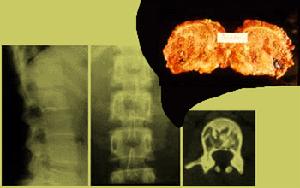

肺囊性纖維化病理粘稠分泌物阻塞胰腺外分泌管,早期出現胰管擴張、腺泡擴大形成囊腫,繼以廣泛纖維化伴細胞浸潤、萎縮,引起糖尿病。外胰腺管阻塞,胰腺酶包括胰蛋白酶、脂肪酶和澱粉酶的分泌不足或缺乏,導致消化、特別是脂肪吸收不良。

肝臟內小膽管被粘液堵塞,引起多小葉性肝硬化、門靜脈高壓和肝功能損害,並可並發脾功能亢進。膽道阻塞可引起黃疸。膽汁缺乏對脂類的消化、脂溶性維生素的吸收、胰液和腸液的消化作用以及腸蠕動都有不良影響。粘液可使腸道上皮剝脫,結構破壞。新生兒在迴腸末端發生胎糞梗阻,為早期常見表現。汗腺分泌中氯化鈉含量明顯增高。輸精管發生纖維化阻塞,失去生育能力。女性生殖能力減退。